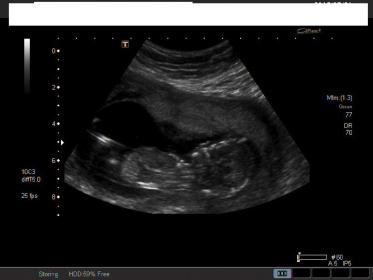

I haven't been on here for awhile. It became too much for me to think about this baby's gender everyday. I couldn't do it. It's so hard this GD. It reared up again today for our ultrasound. It's 14 weeks so I thought they would be able to guess - they didn't tell me anything. I don't even think I have any clear nub shots. Any guesses would be good - Why can't I see a nub!!! UGH....I hope everyone is doing well and getting the DG!!Attachment 26328Attachment 26329